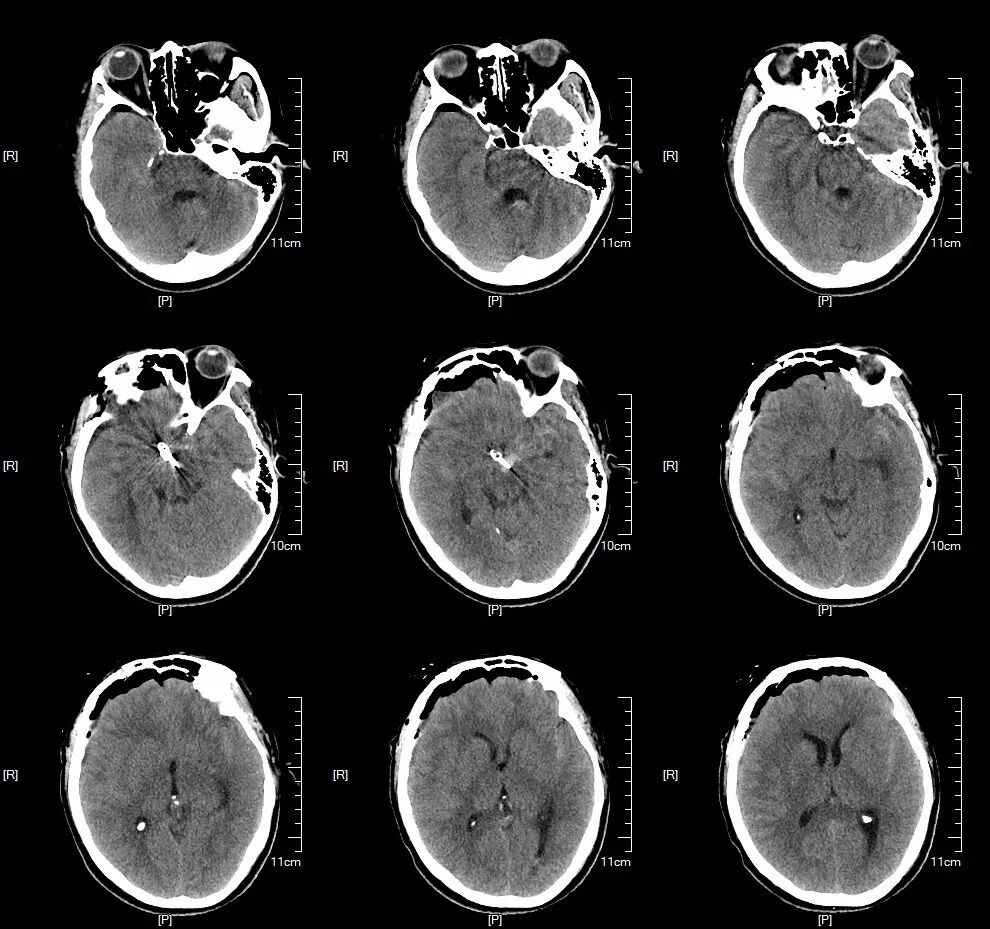

术前CT:脑干周围、双侧侧裂池、后纵裂广泛高密度影,蛛网膜下腔出血。(图2-1)

图2-1. 入院头颅CT检查提示广泛的蛛网膜下腔出血